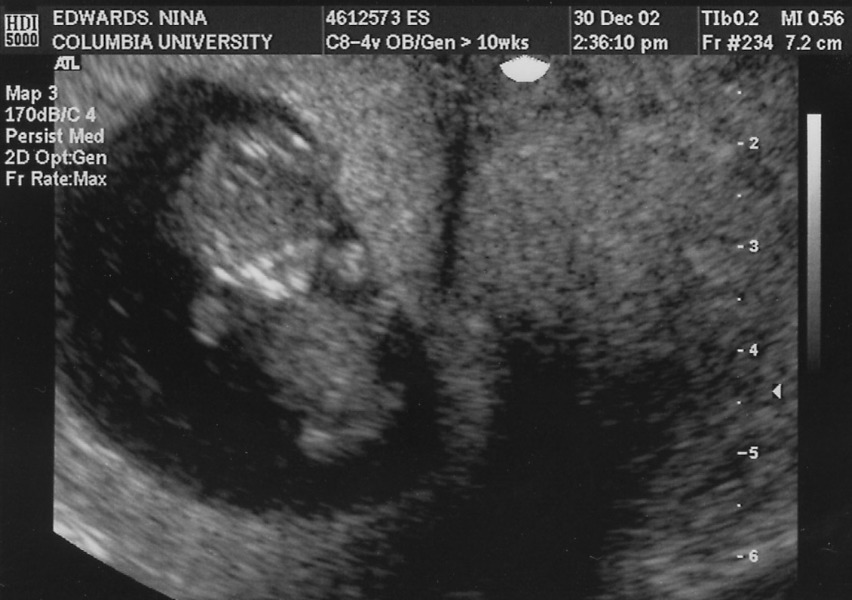

He's the alien floating just left of center.